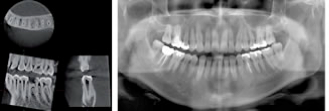

デジタルレントゲン・CT装置

CTでは細かい輪切りの写真を撮れるので、通常のレントゲン写真では診断することのできない3次元的な位置関係を見ることが可能です.

親知らずの抜歯やインプラント手術の際に安心して治療を受けて頂くことができます.